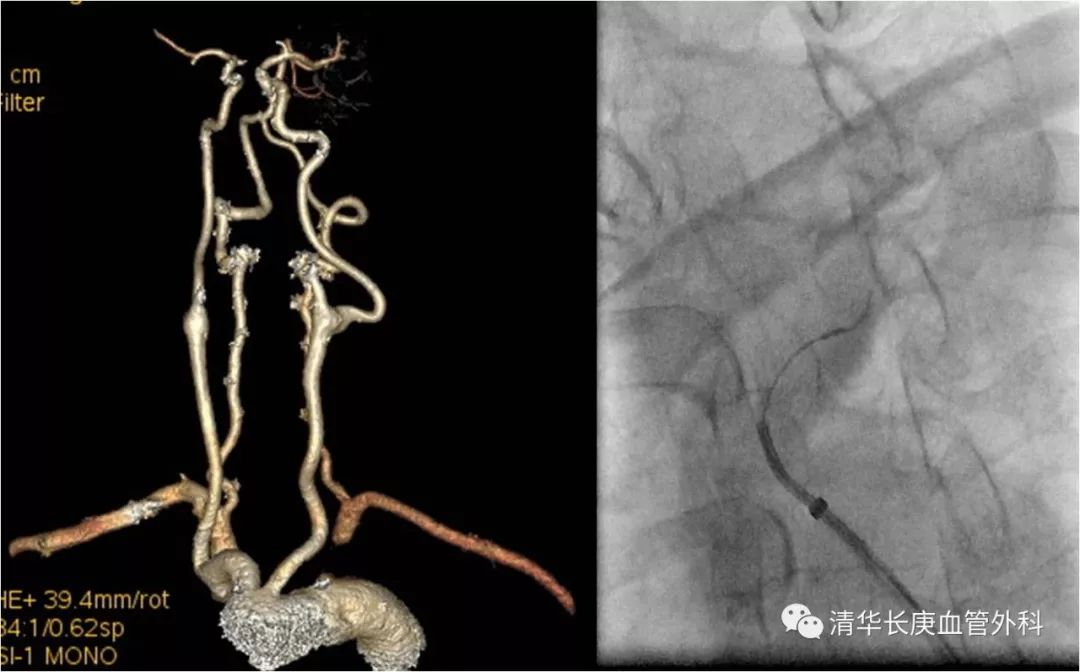

赵克强副主任医师,以典型病例录播形式,向学员们分享了弓上动脉病变的治疗,包括锁骨下动脉闭塞、复杂弓型颈动脉支架的入路建立、多发病变、串联病变的治疗策略,以及弓上病变围术期管理、术中技巧、常见并发症及预防措施;学员们积极踊跃、畅所欲言、交流心得,对弓上病变的诊治有了进一步的认识、体会。

锁骨下动脉闭塞,长鞘+椎管+CXI+V18同轴系统通过病变

双导丝技术

不友好弓型的入路建立